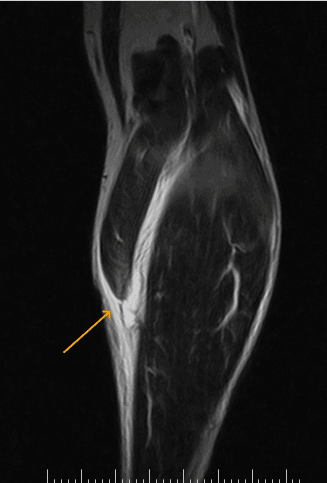

Sintomas e Diagnóstico com MRI

Diagnóstico: físico (defeito, calf-raise). MRI tennis leg diagnóstico edema/retração; ultrassom gradua tear/hematoma, exclui DVT (10%, US Doppler), Aquiles (Thompson). Modern Orthopedics.